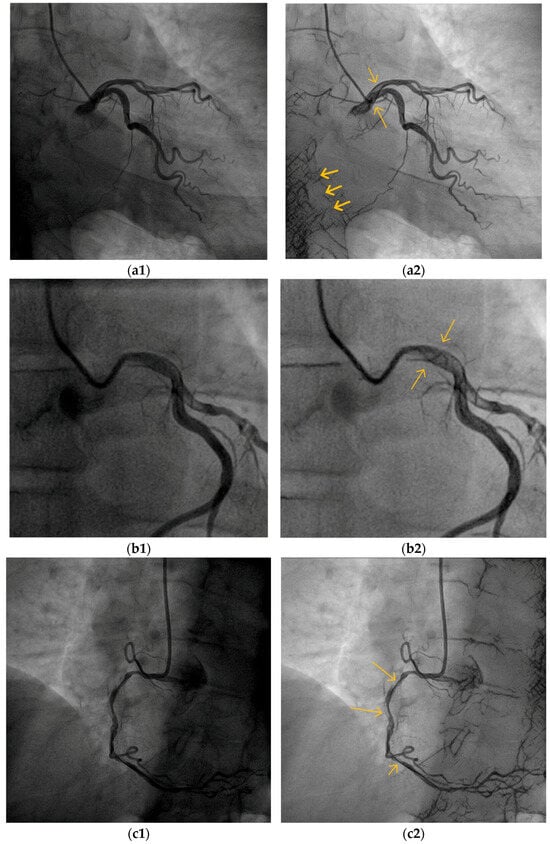

5.2. Blood Vessel Interiors

5.3. Small Blood Vessels

5.4. Low-Contrast Agent, Low-Radiation, and No Contrast Agent